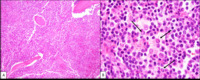

Lymphoplasmacytic lymphoma - Bone core biopsy

A bone core biopsy shows diffuse infiltration by small lymphocytes and plasma cells (A). Dutcher bodies (intra-nuclear pseudo-inclusions comprised of immunoglobulin) are readily identified (B).